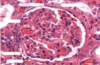

Which part of the kidney is this?

Kidney: Cortex

Renal corpuscles (Bowman’s capsule: simple squamous epithelium)

Proximal convoluted tubules (cuboidal+ microvilli)

Distal convoluted tubules (cuboidal)

Collecting tubule (cuboidal)